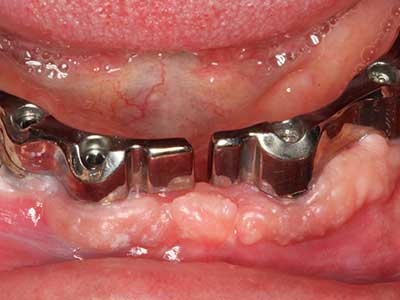

Fig. 14: Incorporación de cuatro implantes RSX cónicos (Bego Implant Systems, Bremen).

Fig. 15: El control radiológico realizado al cabo de un año muestra una estabilidad del nivel óseo.

Fig. 16: También condiciones intraorales estables con incorporación de los implantes en la encía queratinizada.

Fig. 17: Tomografía computarizada de un osteoma de crecimiento progresivo ...